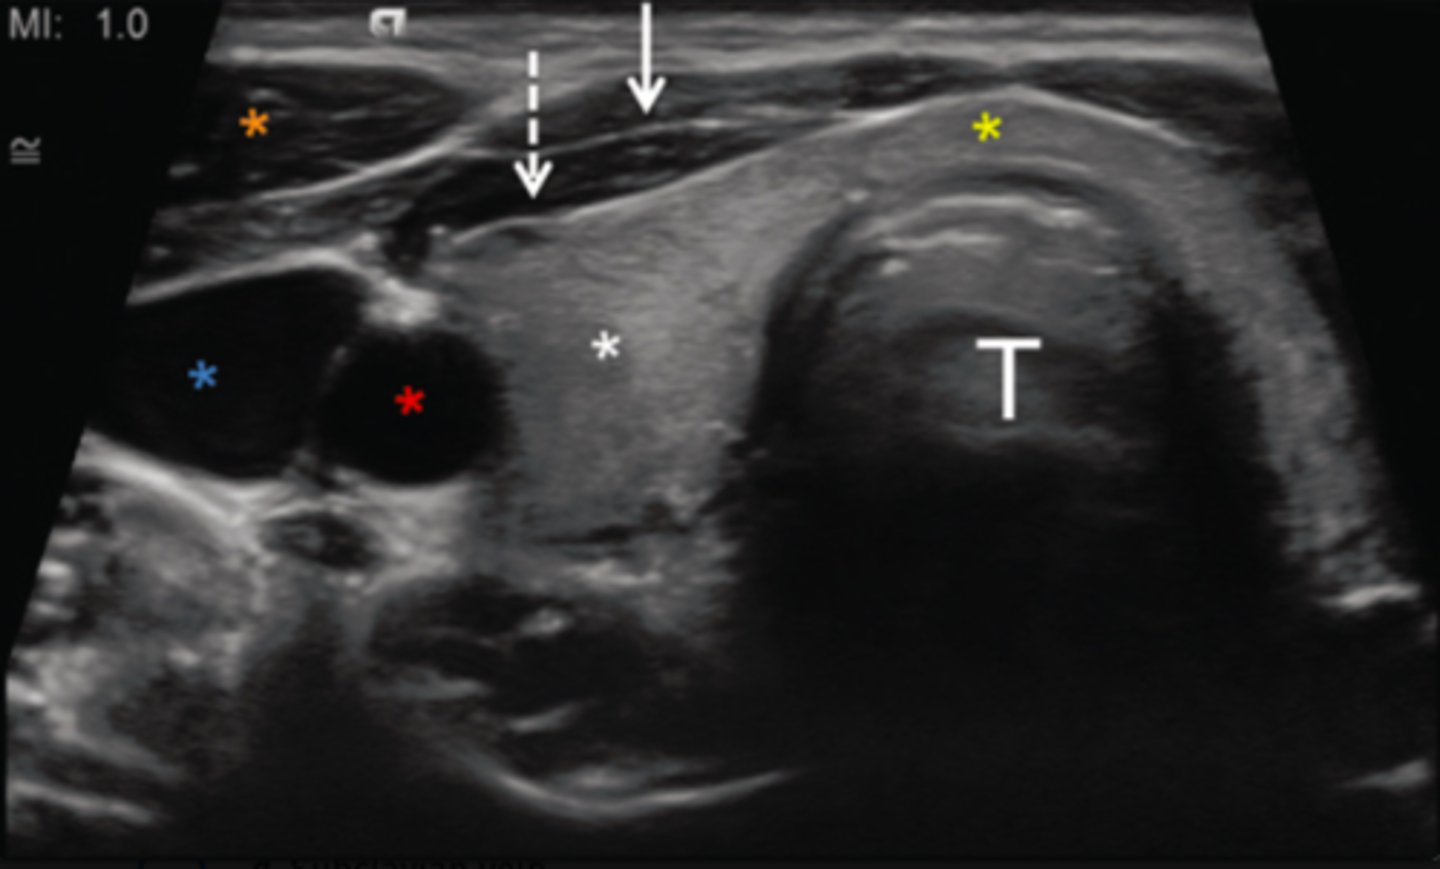

8. What does the red asterisk in Figure 12-25 indicate?

9. What does the blue asterisk in Figure 12-25 indicate?

d. Internal jugular vein

10. What does the orange asterisk in Figure 12-25 indicate?

a. Right longus colli muscle

b. Right sternocleidomastoid muscle

c. Left longus colli muscle

d. Left sternocleidomastoid muscle